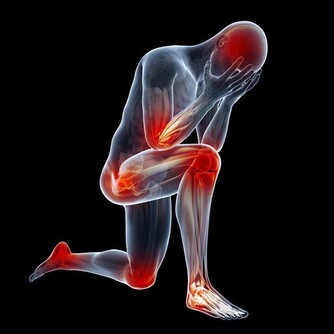

上面說了猝死的內因,那猝死的外因又是什​​麼呢?無非是負面情緒、較劇烈的體力活動或過度疲勞,外傷,暴飲暴食,用力排便,飲酒吸煙等。